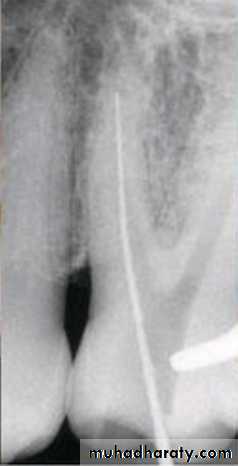

Step-back technique

After determining the master apical file, the succeeding larger files are shortened by 0.5 or 1.0 mm increments from the previous file length.This step-back process creates a flared, tapering preparation while reducing procedural errors.

The step-back preparation is superior to standardized technique in debridement and maintaining the canal shape.